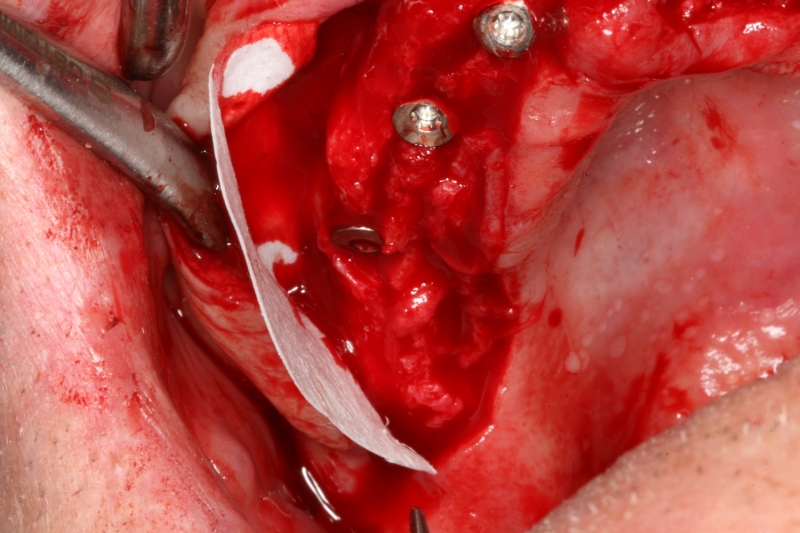

08/10 - Re-entry surgery in combination with vestibuloplasty to form the vestibulumCircular bone splitting with maxresorb® & collprotect® membrane - PD Dr. J. Neugebauer